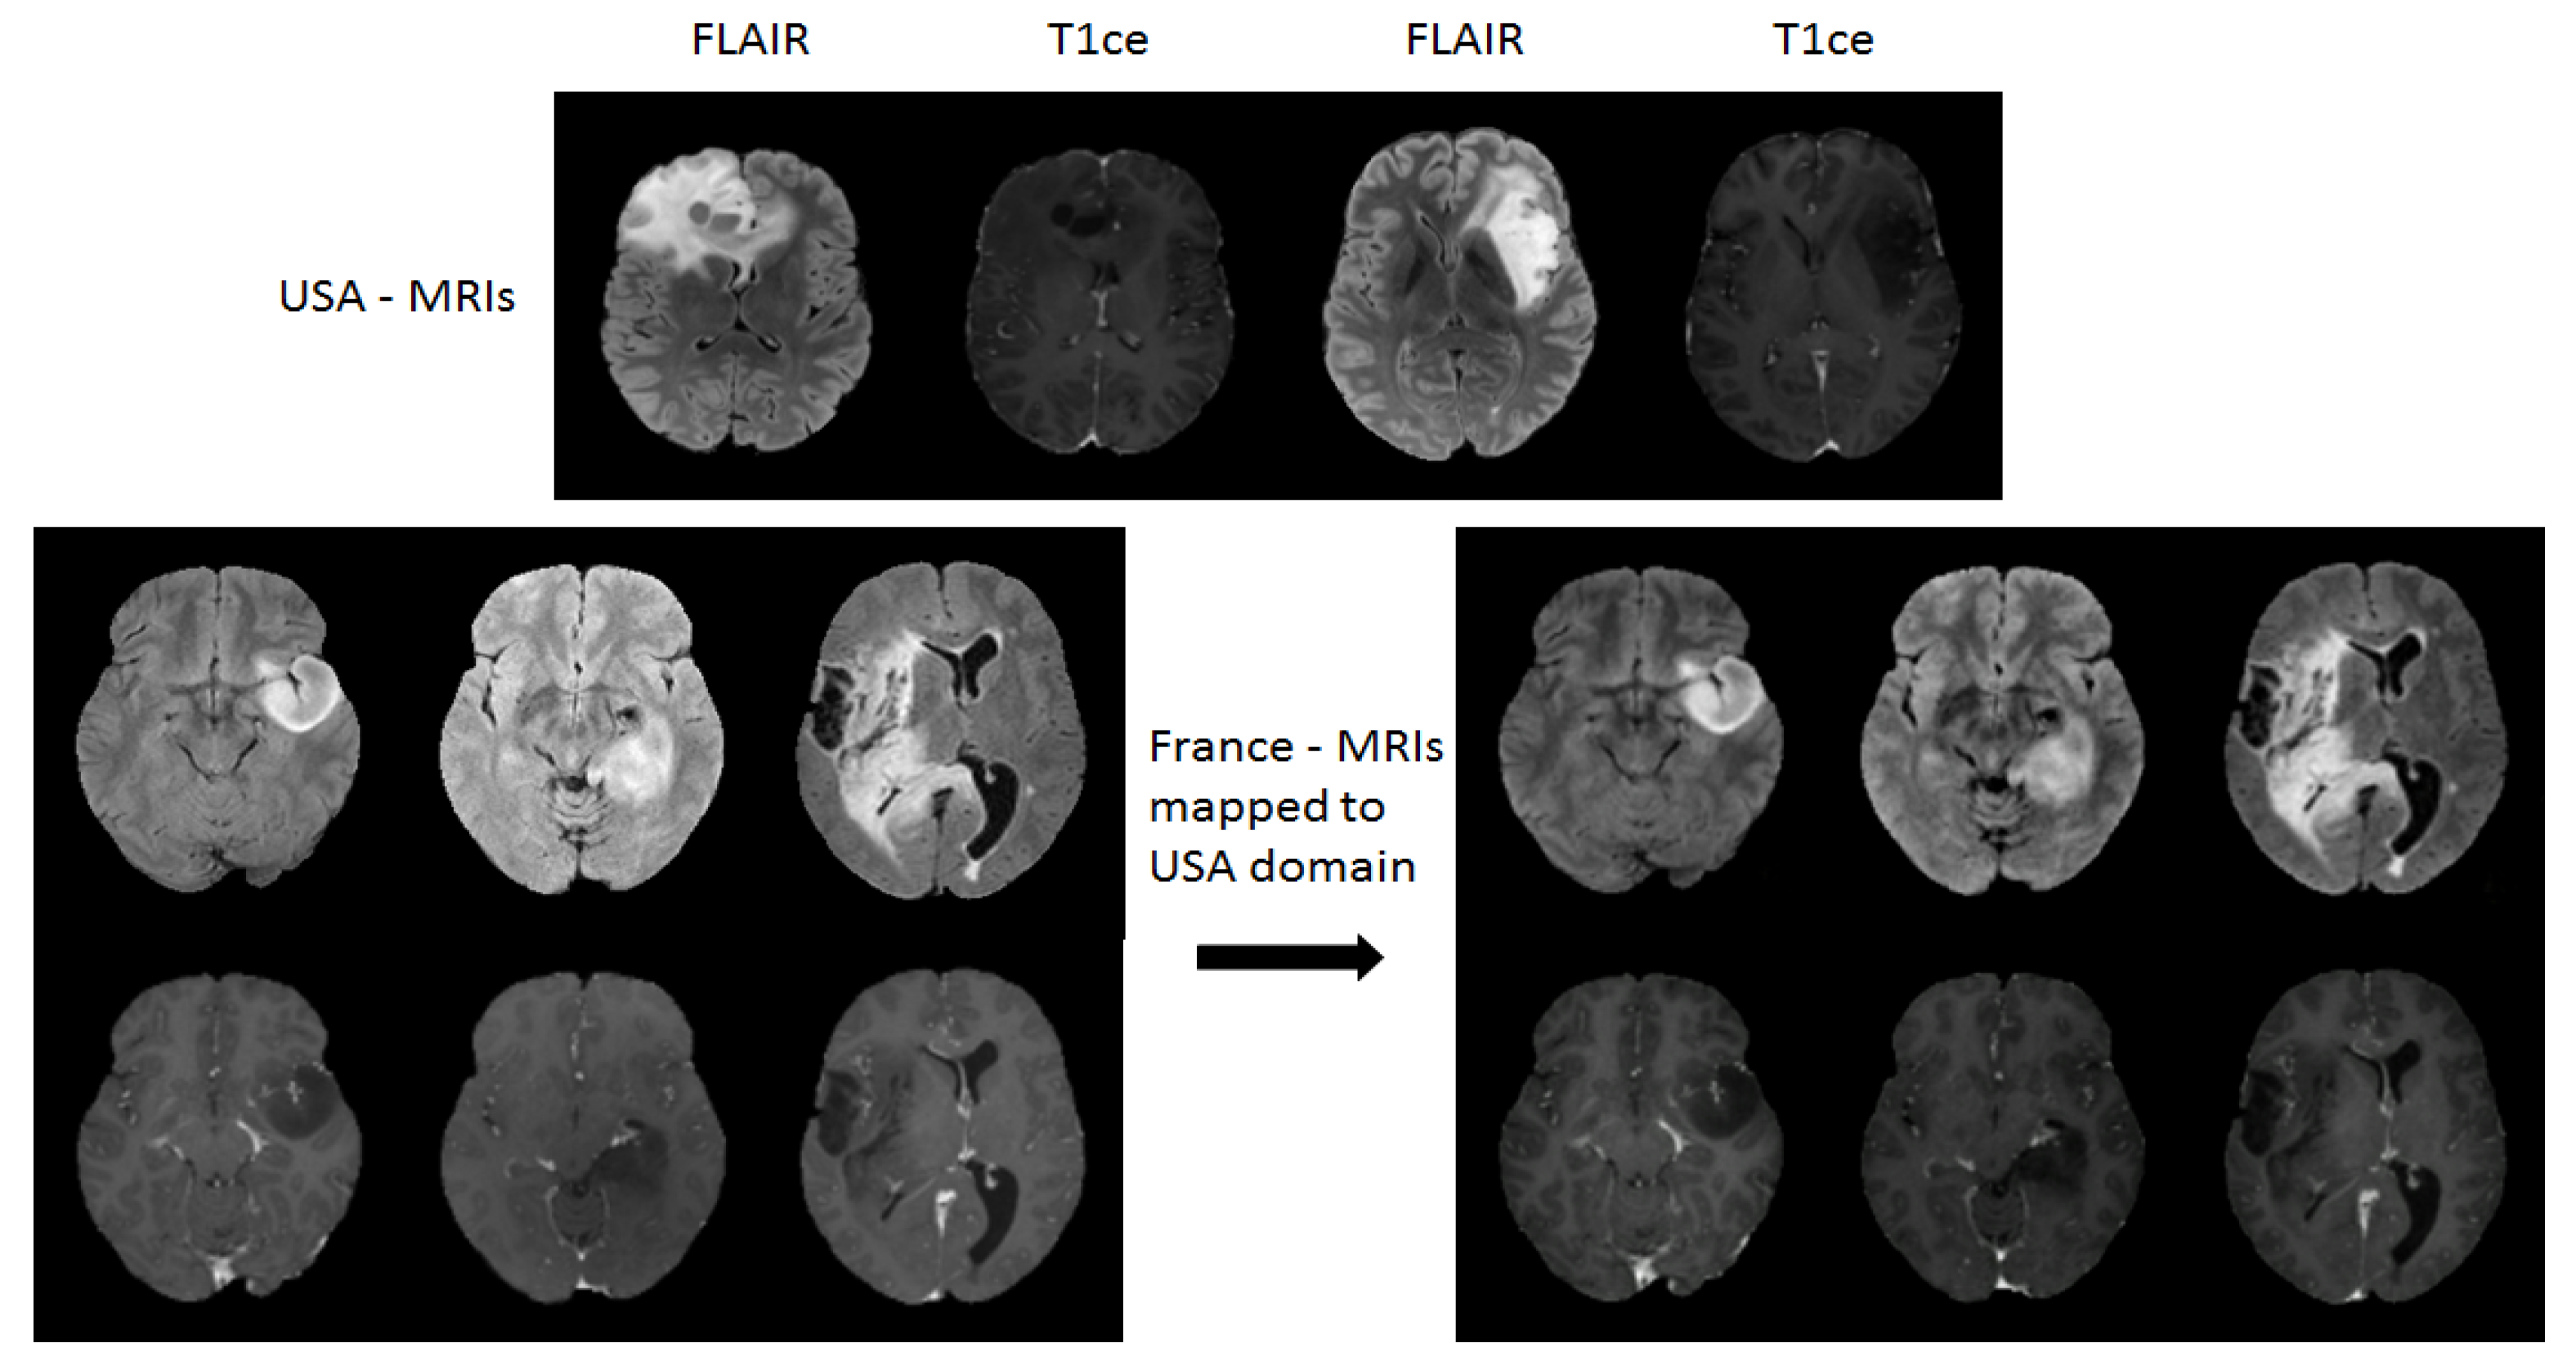

Effect of Domain Mapping: Domain adaption was then applied by mapping the French dataset to the USA data domain. Figure 7 shows an example of visual effect of images before and after the mapping. The domain mapped dataset has also been visually inspected by medical doctors, where domain mapped French dataset showed consistently more similar distribution as that of USA dataset. Moreover, the impact of domain mapping on yielding improved test performance has been discussed in detail in Section 3.3.2.

Figure 7.

Visual inspection of image slices before and after the domain mappings. Top: Examples of FLAIR-MRIs and T1ce-MRIs from USA dataset. Bottom left: 3 original 2D slices of FLAIR-MRIs (1st row) and T1ce-MRIs (2nd row) from France dataset. Bottom right: Domain mapped 2D slices of FLAIR-MRIs (1st row) and slices from T1ce-MRIs (2nd row) from France to USA domain.